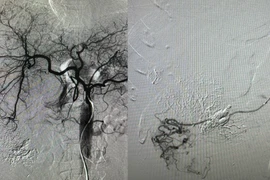

Chỉ khoảng 20% bệnh nhân ung thư gan tại thời điểm chuẩn đoán có thể thực hiện phẫu thuật cắt gan. Đây là kỹ thuật khó nhưng là phương pháp điều trị triệt căn hiệu quả hàng đầu.